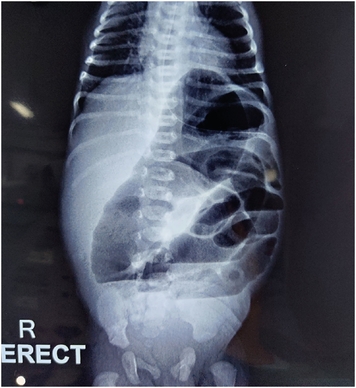

The excised specimen (Fig. 3) on histopathology examination was reported as a dysplastic proximally atretic ileum and a tubular duplication cyst in the fleshy structure fished out from the distal end. Post operative course was uneventful (Fig. 4). Patient was kept nil per oral for 5 days, gradually weaned to full feeds and discharged by 9th post operative day. On follow up visit he was doing well.

Fig. 3

Complete resected specimen of proximal (dilated) and distal atretic bowel with the fleshy structure.